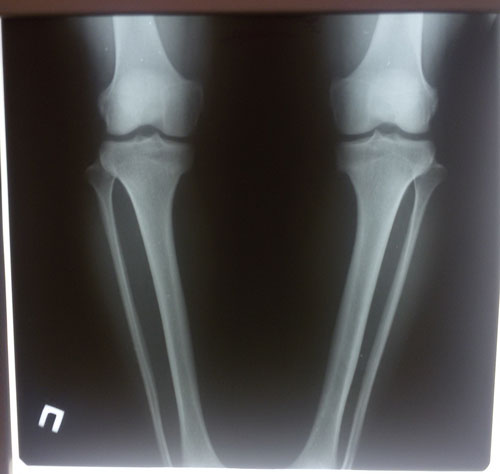

Диагноз: ахондроплазия, варусная деформация обеих голеней 155 градусов.

26 лет.

Дата операции 08.07.2015г.

Исходник.

рентген до операции.